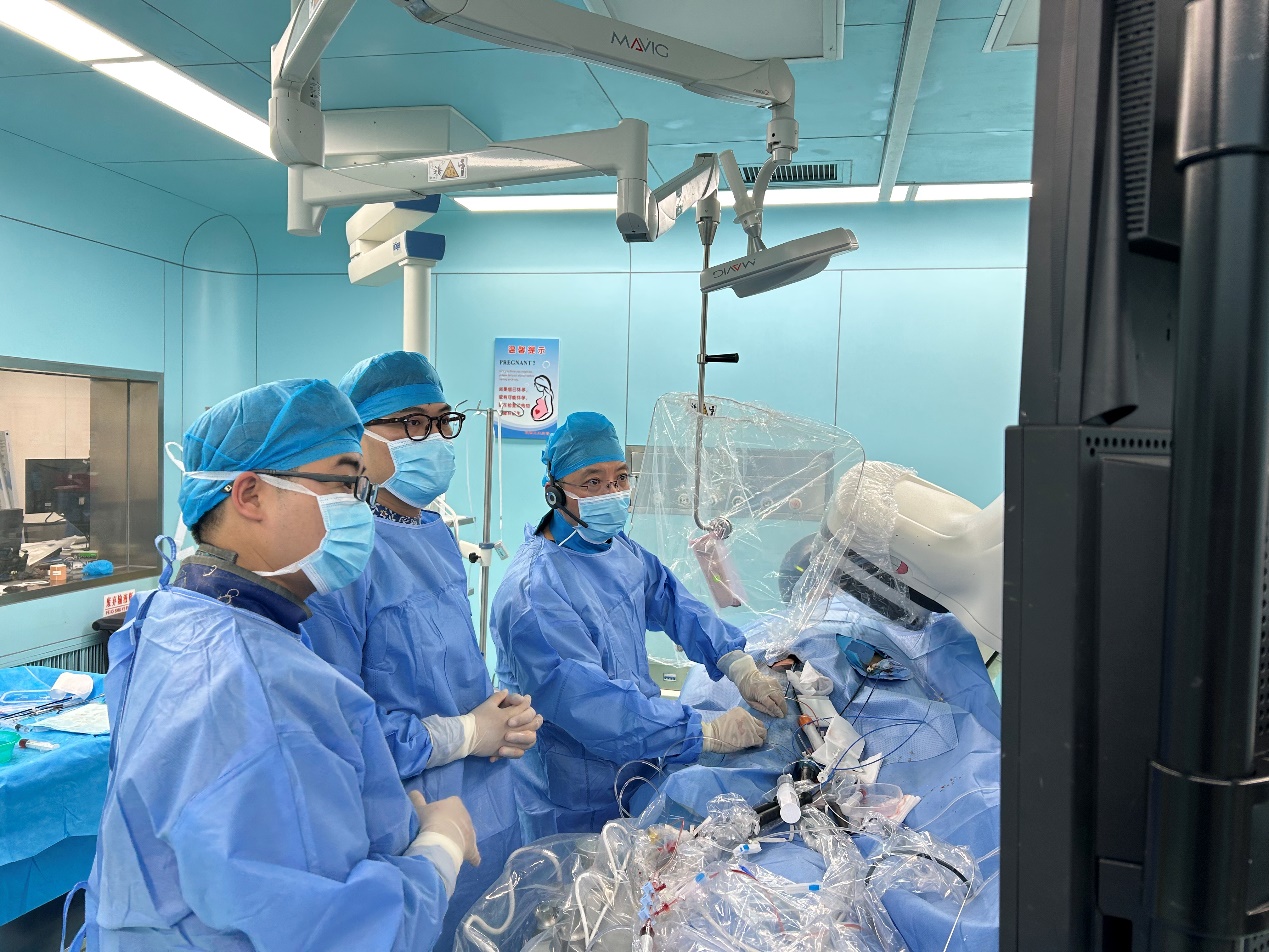

近日,我院心血管内科心律失常诊疗团队在王洪涛副主任的带领下,成功为一位罕见的镜面右位心患者实施了房颤射频消融联合左心耳封堵一站式手术,标志着我院在复杂心律失常疾病治疗领域取得了新的突破。为相关患者带来了崭新的希望曙光。

面对这一复杂病例,我院心律失常诊疗团队在郑强荪院长、王洪涛副主任的指导下,进行了详尽的术前讨论和评估。王洪涛教授表示:“镜面右位心合并房颤的病例极为罕见,手术难度极大。我们需要充分利用现代医疗技术,为患者制定个性化的治疗方案。”结合患者病史、检查结果及技术能力,团队制定了周密的手术方案。

手术过程中,王洪涛教授亲自操刀,充分利用CARTO 3三维标测系统,实现了精准定位和消融,成功为患者实施了房颤射频消融术。随后,团队又克服了镜面右位心带来的操作困难,使用新一代国产左心耳封堵器LACbes成功完成了左心耳封堵术,有效预防了卒中的发生。王洪涛教授解释:“房颤射频消融术能够消除房颤的症状,而左心耳封堵术则能够闭合房颤患者血栓发生的根源部位,两者结合能够大大降低患者的卒中和出血风险。”

整个手术过程历时数小时,团队凭借精湛的技术和丰富的经验,确保了手术的顺利进行。术后,患者生命体征平稳,无并发症发生,恢复情况良好。王洪涛教授对手术效果表示满意:“患者的恢复情况非常理想,这标志着我们医院在复杂心律失常疾病治疗方面迈上了新的台阶。”